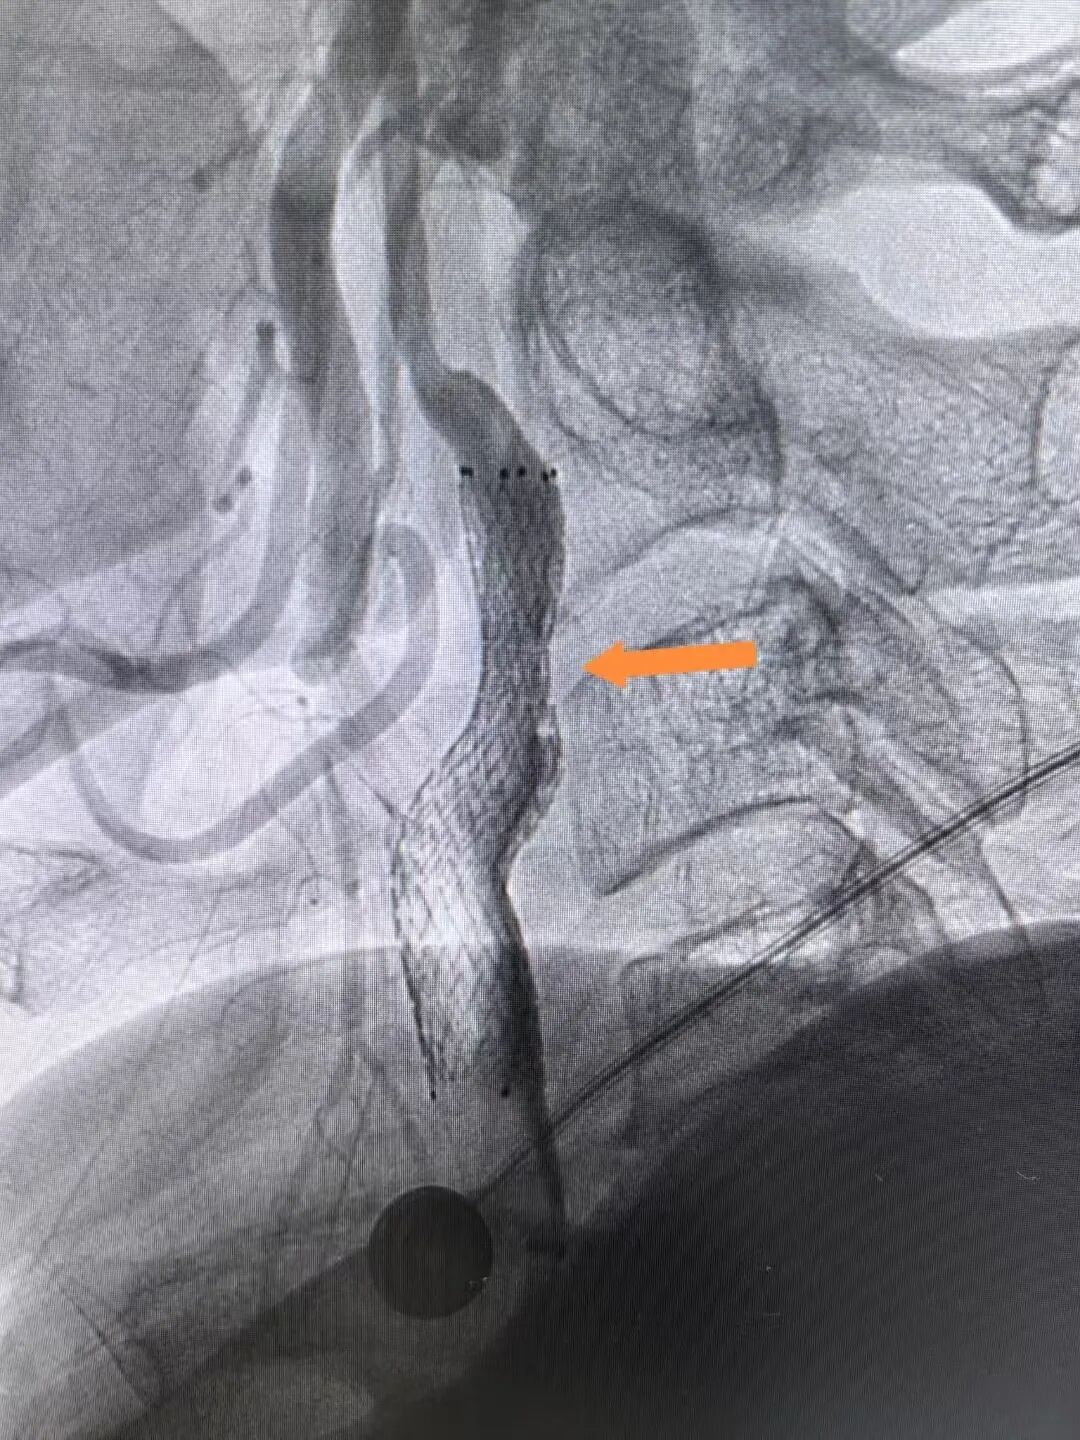

支架植入后,患者前降支血管血流恢复通畅

在征得家属同意后,医疗团队优先为罗先生实施心血管手术。然而,就在准备植入支架的紧要关头,患者突发室颤导致心跳骤停。经验丰富的手术团队临危不乱,立即启动应急预案,果断实施胸外按压,并给予两次精准电击除颤。在惊心动魄的几分钟后,罗先生的心脏终于恢复搏动。稳住患者生命体征后,玉溪市中山医院心内科业务主任李驹凭借精湛的医术,精准、迅速地将支架植入堵塞血管。随着支架成功撑开,停滞的血流瞬间恢复通畅,罗先生的心脏危机暂时得以化解。

同时,王和平教授紧急到院,带领诊疗团队采用股动脉穿刺微创通路,在DSA引导下精准植入支架,40分钟内解除颈动脉闭塞,造影显示颈动脉血流恢复通畅,术后次日患者即可下床活动。